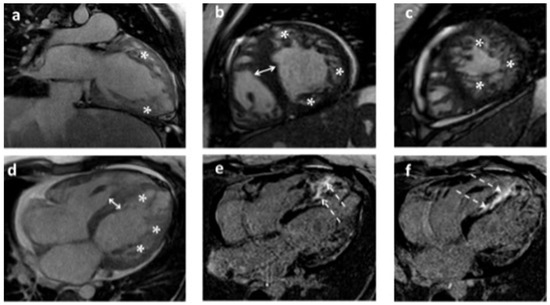

Genetic Spectrum, Clinical Characteristics, and Molecular Pathogenesis of Hypertrophic Cardiomyopathy Requiring Heart Transplantation

by Sofiya Andreeva, Lyubov Korneva, Mariya Marusova, Yulia Sazonova, Alexandra Gudkova, Anna Streltsova, Svetlana Fetisova, Maria Simonenko, Anna Fanta, Andrei Semenov, Maria Bortsova, Lubov Mitrofanova, Olga Moiseeva, Alexandr Bobylev, Lidiya Gavrilova, Ivan Vikhlyantsev, Petr Fedotov and Anna Kostareva

J. Cardiovasc. Dev. Dis. 2025, 12(12), 499; https://doi.org/10.3390/jcdd12120499 - 17 Dec 2025

Hypertrophic cardiomyopathy (HCM) progressing to end-stage heart failure and heart transplantation (HT) is a rare clinical scenario with an insufficiently explored genetic background. In this single-center retrospective cohort study, we aimed to characterize the genetic spectrum, variants of HCM adverse remodeling, and aspects [...] Read more.

Hypertrophic cardiomyopathy (HCM) progressing to end-stage heart failure and heart transplantation (HT) is a rare clinical scenario with an insufficiently explored genetic background. In this single-center retrospective cohort study, we aimed to characterize the genetic spectrum, variants of HCM adverse remodeling, and aspects of molecular pathogenesis of this subgroup. The study included 14 patients (9 females), among whom 10 developed a dilated/hypokinetic phenotype and 4 a restrictive phenotype. In 13 patients (93%), at least one pathogenic or likely pathogenic genetic variant was identified. Dilated remodeling/hypokinesis was associated with loss-of-function variants in LAMP2 (3) in females, ALPK3homo (1), MYH7 (1), MYBPC3 (1), a heterozygous missense variant in TRIM63 (1), FLNCtv (1), TTNtv (2). For the latter two, electrophoretic analysis of titin isoform composition and protein content in myocardial fragments from explanted hearts confirmed the functional significance of TTN gene variants. The restrictive phenotype in the adult group was associated with carriage of multiple pathogenic sarcomere gene variants: MYL3homo (1), MYBPC3+TPM1 (1), an MYH7 converter domain variant (1), and, in one child, with a TNNT2 variant. This findings support HCM progressing to HT is characterized by a higher frequency of variants in non-sarcomeric genes and Danon disease compared to the general HCM cohort. Full article

Show Figures

Figure 1